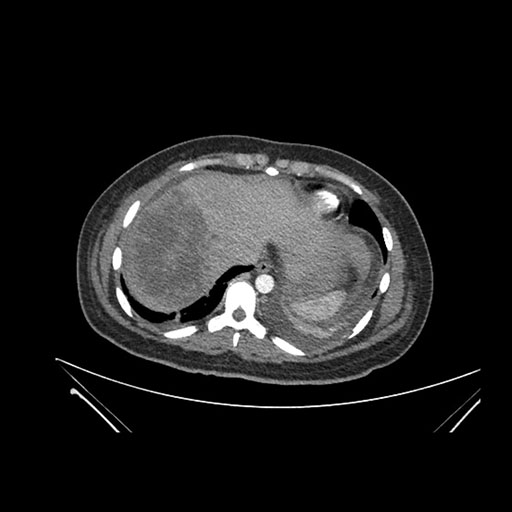

Imaging Analysis

Look through the patient's CT scan to identify any areas of concern for the necessary procedure.

Axial Arterial